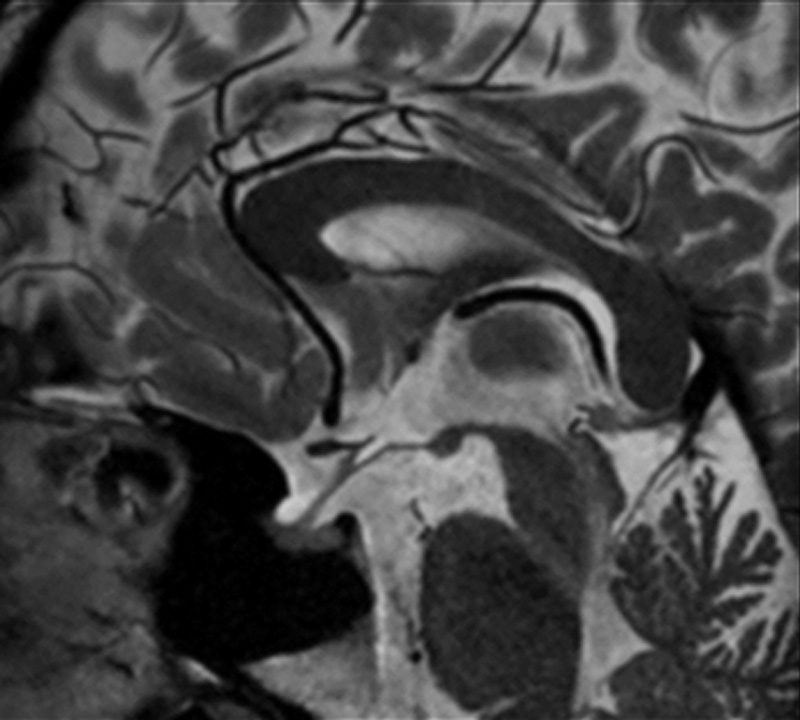

Sag T2w for pituitary

Using a regular head and neck coil, with a collection matrix 256 × 256 setting, imaging can be performed in approximately 1 minute. Structures around the pituitary gland are clearly visible.

Acquisition time: 1:08